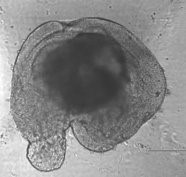

Bone Forming Spheroids

Designed for high translatability, closely mimicking human bone regeneration.

Bone regeneration is achieved in just one week, compared to the traditional 4-5 weeks required by conventional 2D systems.